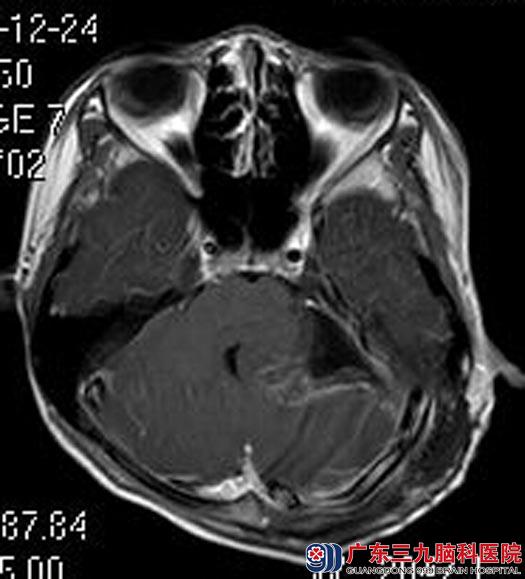

得知是脑瘤,小豪的父母不敢耽误,带着他来到广东三九脑科医院综合神经外科。进一步头颅MR检查:左侧桥小脑角区示囊实性占位病变,大小约32.3mm×39.3mm×33.6mm,考虑脑膜瘤可能性大。

由鲁明主任主刀,在全麻下行左侧桥小脑角区肿瘤切除术,术中显微镜下见肿瘤位于左侧桥小脑角,质软,灰白色,血供少,予镜下全切,中后组颅神经保留完好,术后小豪未再出现呕吐等类似“胃炎”症状,已康复出院。术后病理结果:非典型性脑膜瘤(WHO II级)。